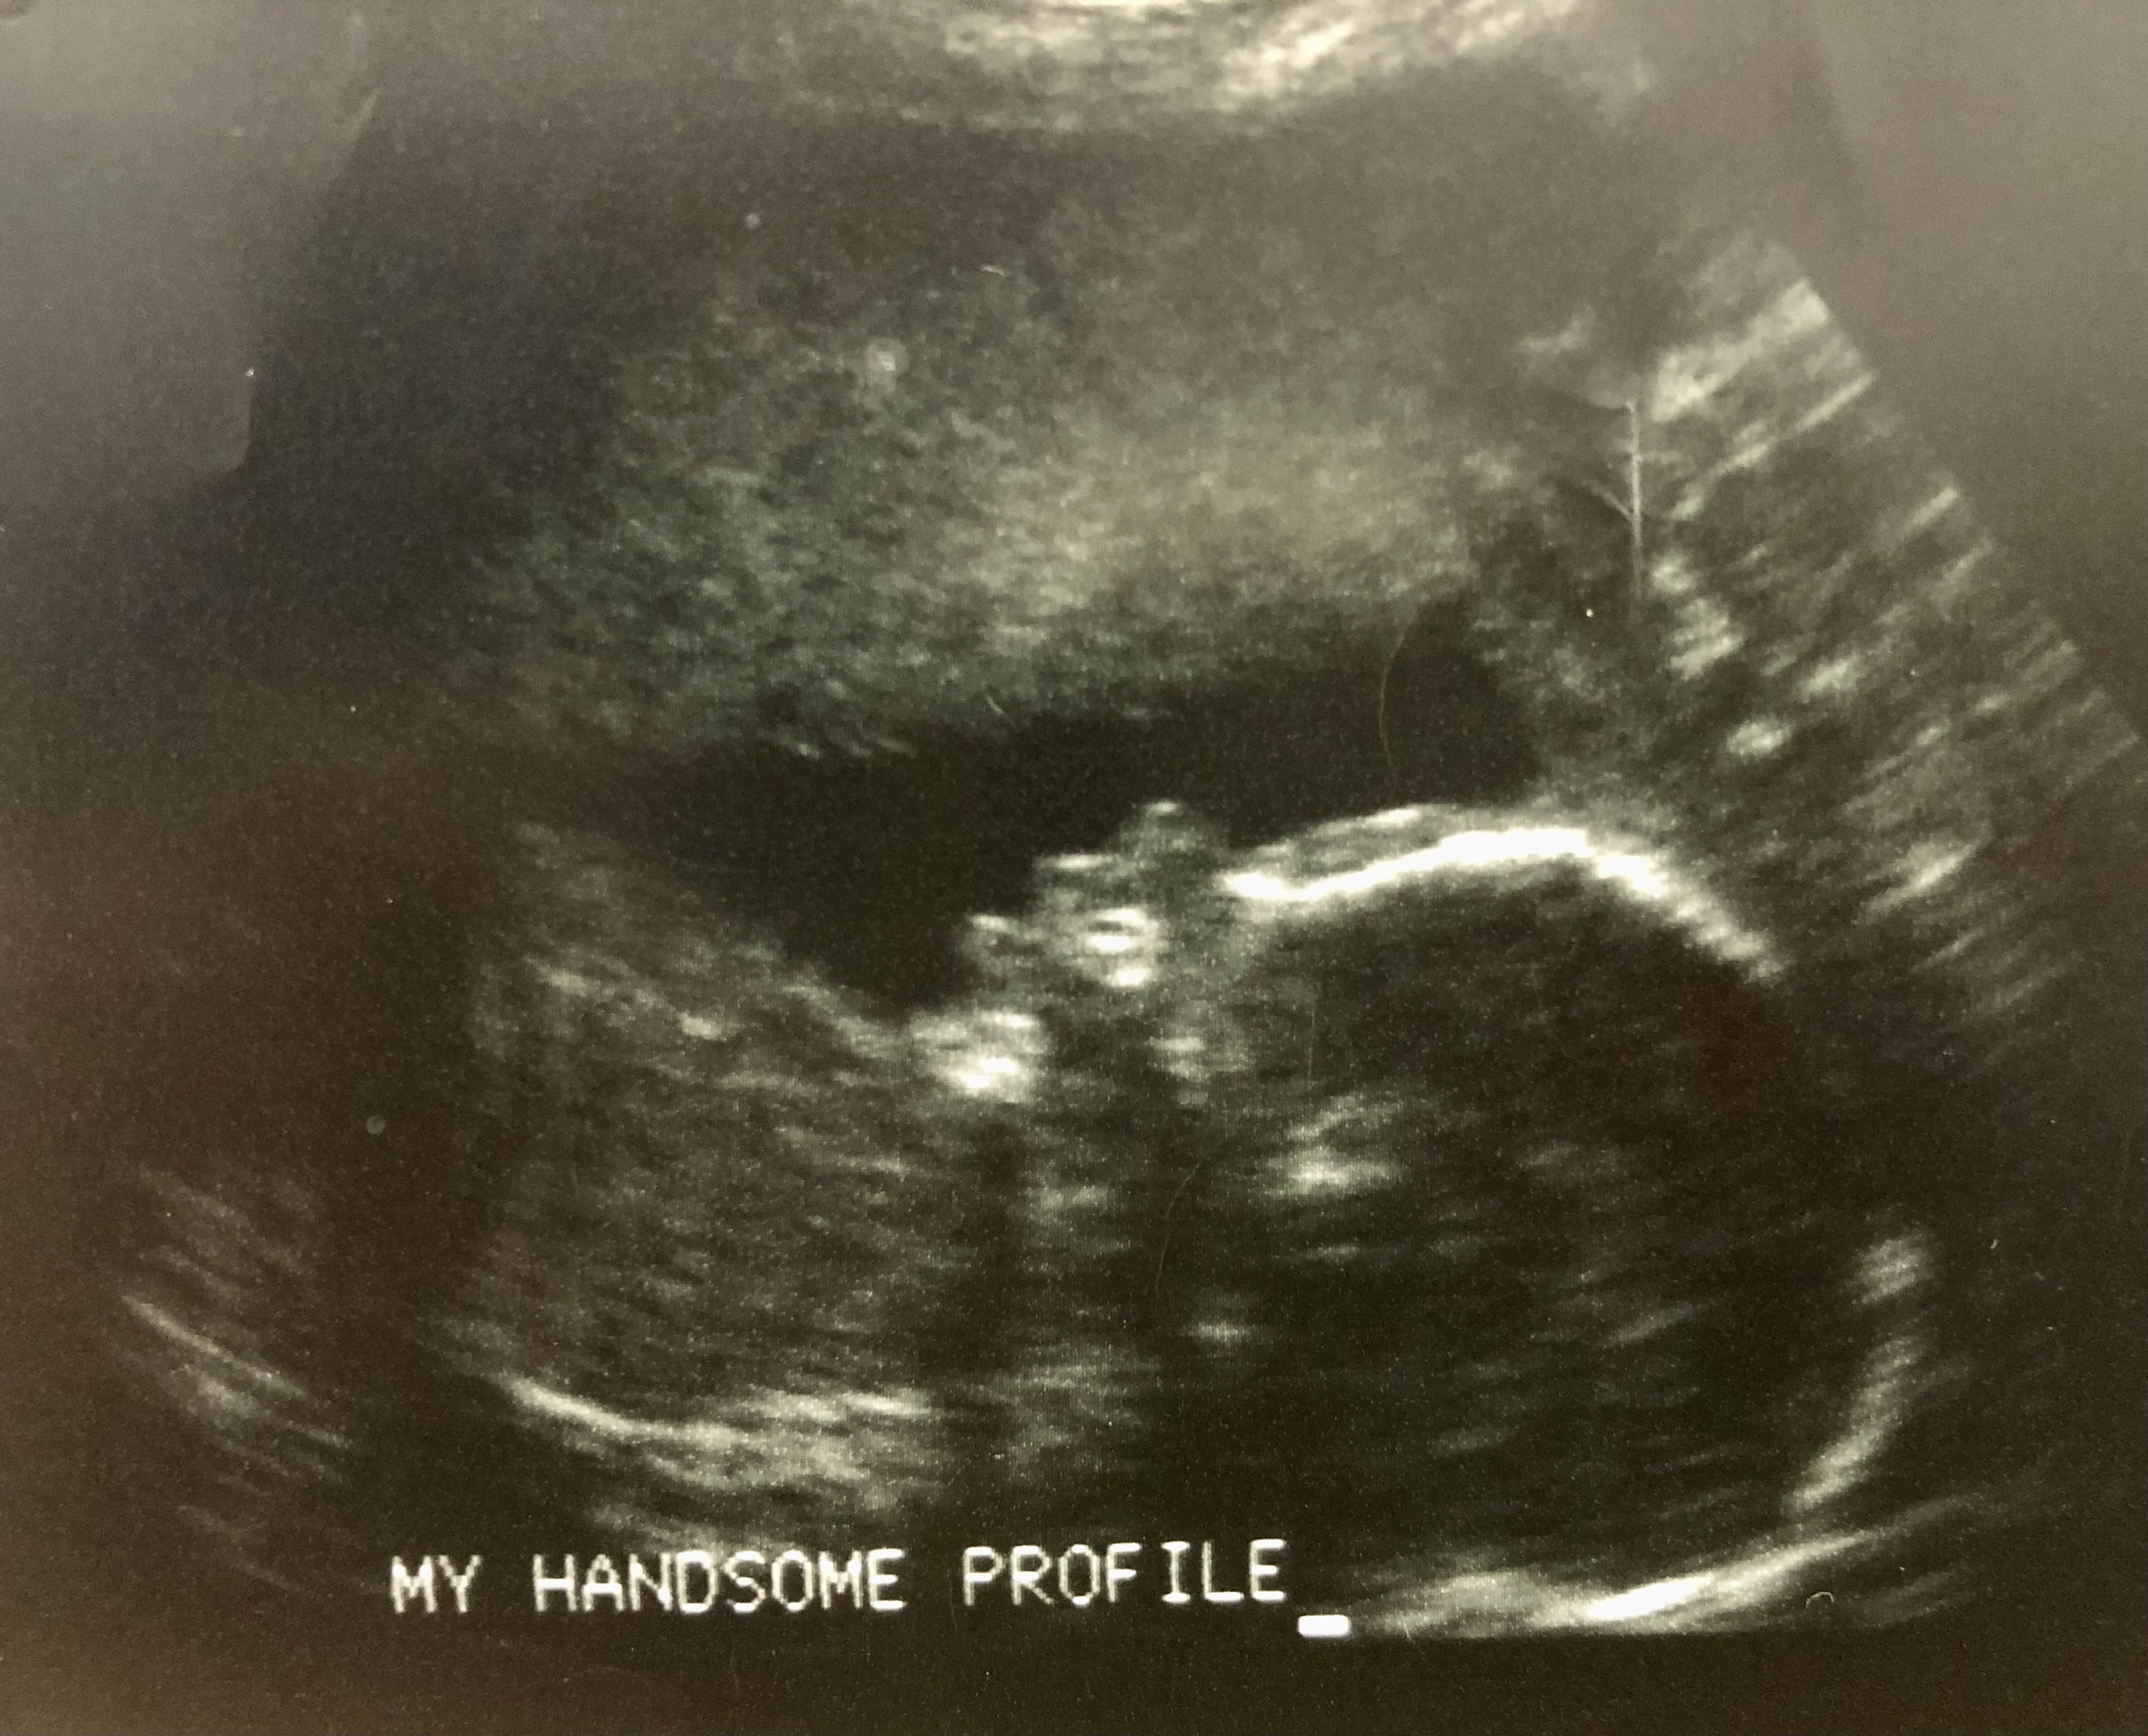

My first sonogram. I’m four months pregnant with Sam (though we haven’t chosen his name yet) when we find out we’re having a boy.

“There.” The nurse points to the monitor, to the tiny, fluttering heart. “Do you see it beating?”

David and I squint at the tiny, convulsing blob on the black-and-white screen.